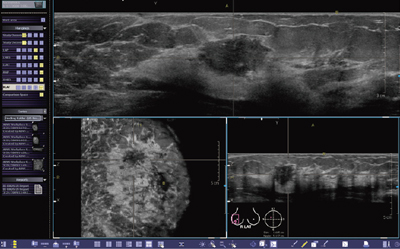

取得されたボリュームデータセットを基にして,オンライン接続されたワークステーション上で,縦断面・横断面・冠状断面を同時に観察できます(図3)。さらに断面の移動や回転も容易であり,納得できるまで何度でもやり直しが可能です。また,ダブルチェックで診断精度を高めることも容易です。

図3 専用ワークステーションによる画像表示例